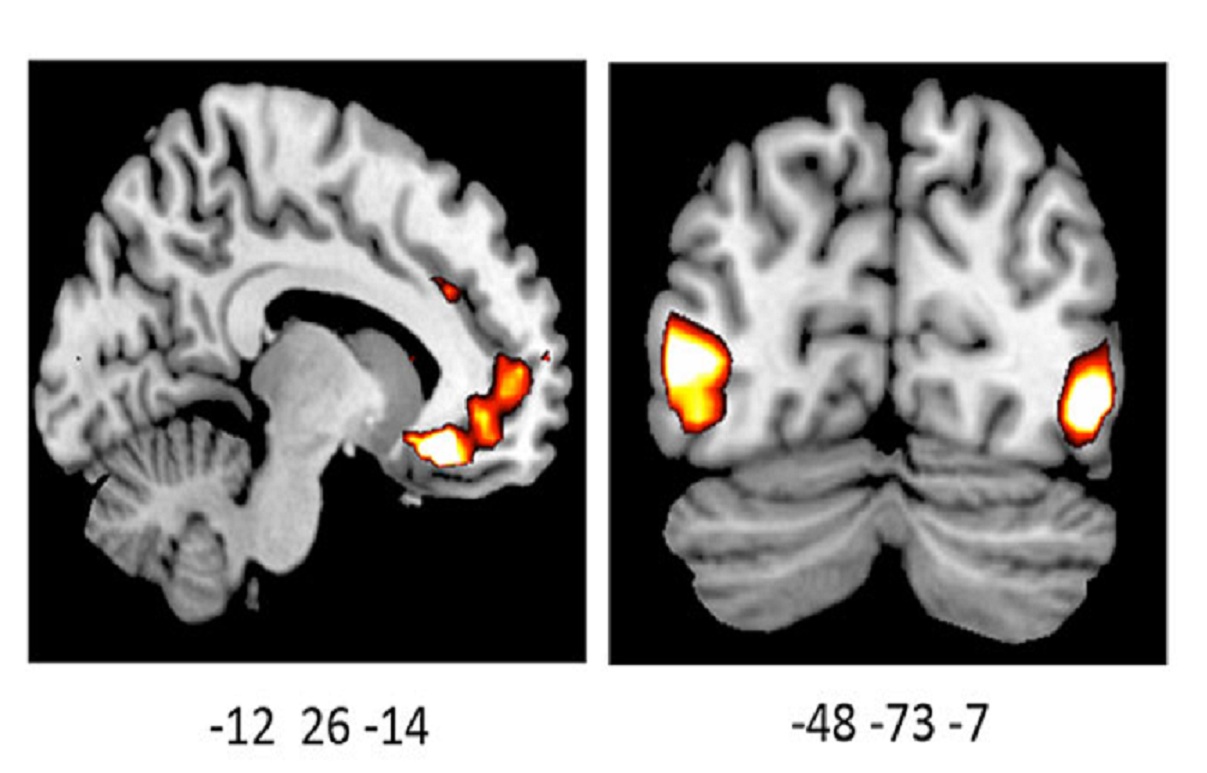

La imagen muestra una actividad incrementada en los cerebros de los portadores de la variante por delación del gen ADRA2b. Fuente: UBC.

El estudio, publicado recientemente en The Journal of Neuroscience, reveló que los portadores de una determinada variación genética percibían imágenes positivas y negativas con mayor intensidad, y presentaban una actividad cerebral aumentada en ciertas regiones del cerebro ante dichas imágenes.

El presente estudio, por su parte, es el primero que utiliza imágenes del cerebro para averiguar cómo este gen afecta a la forma en que la gente percibe vívidamente el mundo que le rodea. Incluso para Todd, los resultados han sido sorprendentes.

El estudio, publicado recientemente en The Journal of Neuroscience, reveló que los portadores de una determinada variación genética percibían imágenes positivas y negativas con mayor intensidad, y presentaban una actividad cerebral aumentada en ciertas regiones del cerebro ante dichas imágenes.

La investigadora analizó los cerebros de 39 participantes, 21 de los cuales eran portadores de la variación genética.

De todos los voluntiarios, los portadores de dicha variación mostraron significativamente más actividad en una región del cerebro responsable de la regulación de las emociones, y de la evaluación tanto del placer como de la amenaza.

La investigadora analizó los cerebros de 39 participantes, 21 de los cuales eran portadores de la variación genética.

De todos los voluntiarios, los portadores de dicha variación mostraron significativamente más actividad en una región del cerebro responsable de la regulación de las emociones, y de la evaluación tanto del placer como de la amenaza.